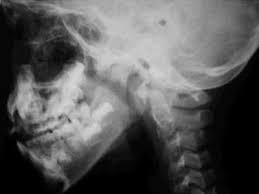

Médicos del Atlanta Medical Center (Estados Unidos) se sorprendieron al hallar una bala la parte trasera del cráneo de una mujer que concurrió para una consulta por dolores de cabeza.

La paciente, de 41 años, no recordaba haber sido baleada, informó el FBI.

Foto 1: ilustrativa